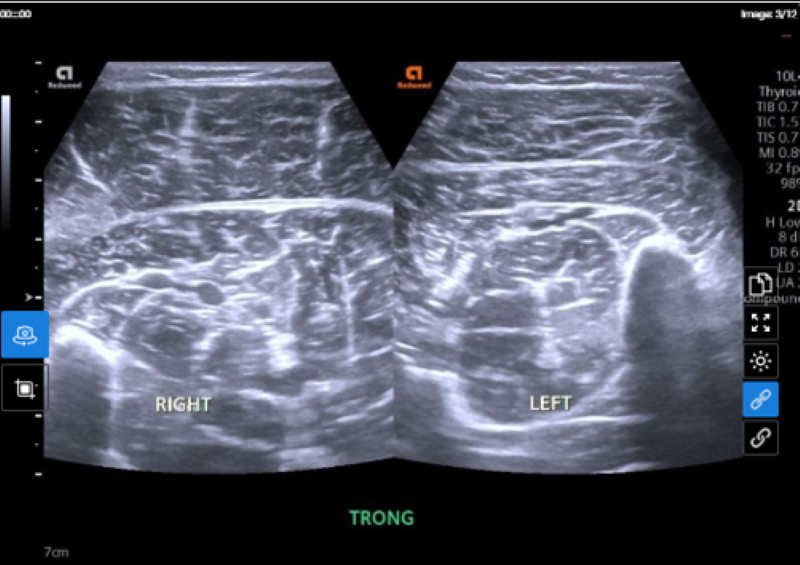

Xét nghiệm virus test nhanh (5 tác nhân) cho kết quả dương tính với cúm A. Đặc biệt, trên hình ảnh siêu âm phần mềm chân phải phát hiện tình trạng phù nề cơ bụng chân trong - ngoài, cơ dép chân phải. Kết quả xét nghiệm men cơ CK total đạt 2419.6 U/L, gấp gần 60 lần mức bình thường. Chẩn đoán xác định, bệnh nhân mắc cúm A có tổn thương tiêu cơ vân cấp.

Bất thường tại chân phải được phát hiện trên hình ảnh siêu âm phần mềm